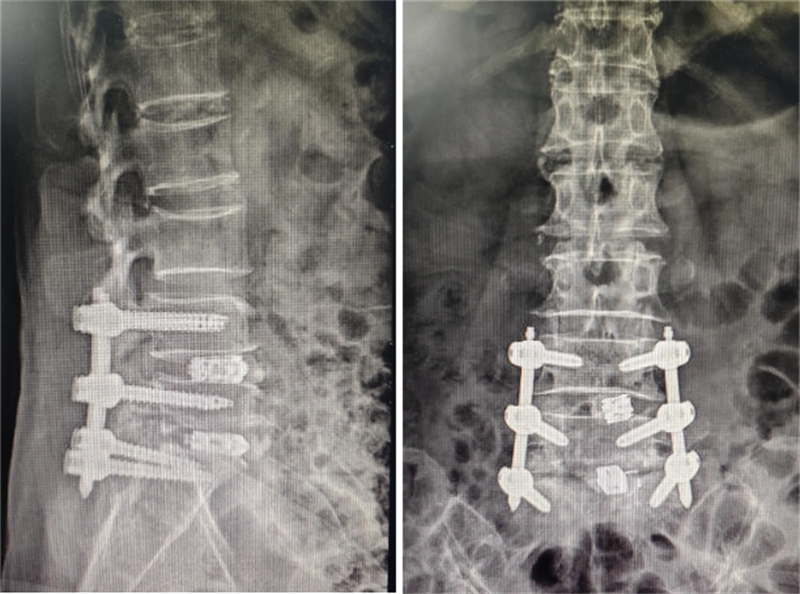

術后影像

手術當天,在機器人的輔助下,所有置釘操作均達到了預期目標,內鏡下的椎間融合也順利完成。術后即刻,許女士便感受到了腰腿疼痛的顯著減輕。在醫護人員的悉心照料下,術后第二天,她就已經能夠在病房內站立并嘗試行走。